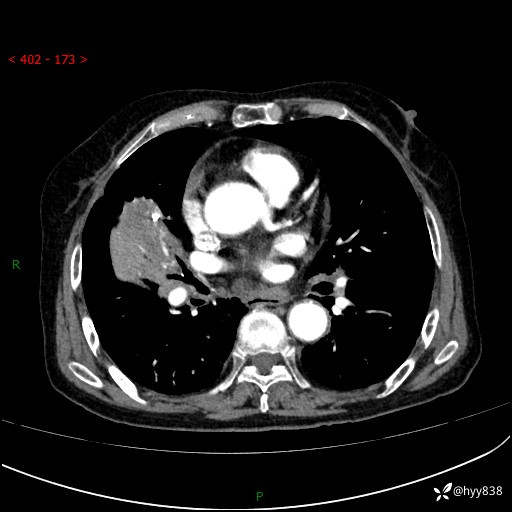

胸部CT增强(外院平扫)